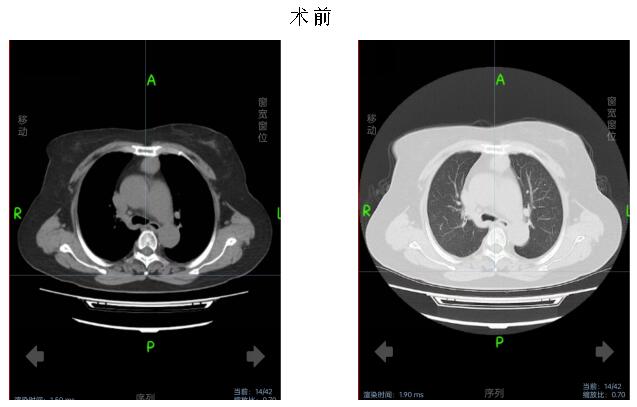

患者女性,70岁,体检发现前纵隔占位性病变遂就诊于市中心医院。入院后完善术前检查,排除手术禁忌症,经胸外科杨斌主任医师、副主任医师李卫国、主治医师车小川讨论病情,并向患者讲明病情并征求患者及家属同意后,积极完善术前准备。

术中,在麻醉手术科配合下,李卫国带领胸外科团队为患者行胸腔镜经剑突肋缘三孔式胸腺病损切除术。术中送冰冻,30分钟后病理报告提示胸腺瘤,术后生命体征平稳,给予镇静止痛、营养支持等对症治疗。术后第3天复查胸部CT未见明显积液积气。患者无特殊不适。